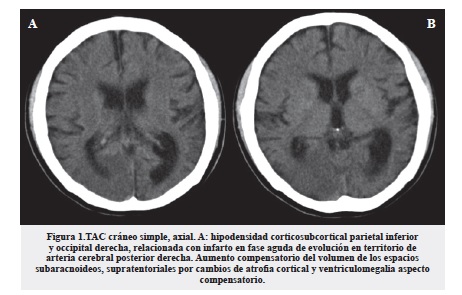

En la TAC cerebral simple como principal hallazgo encontramos una hipodensidad cortico - subcortical parietal inferior y occipital derecha, relacionada con infarto en fase aguda de evolución en territorio de arteria cerebral posterior derecha. Al igual que aumento compensatorio del volumen de los espacios subaracnoideos supratentoriales por cambios de atrofia cortical y ventriculomegalia compensatoria a la pérdida de volumen parenquimatoso (figura 1).